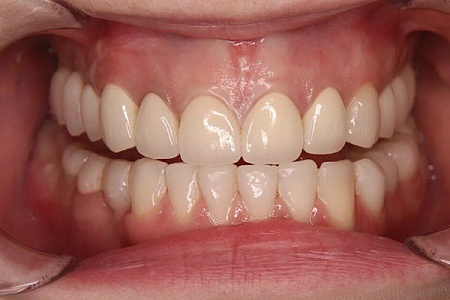

Работы наших врачей